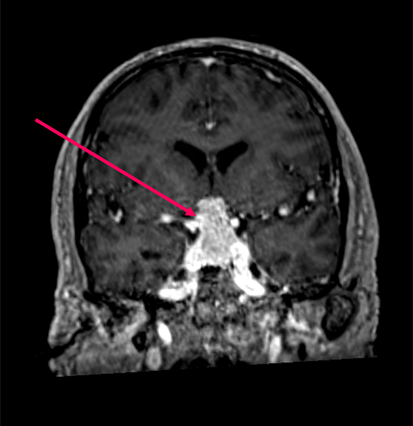

Macroadénome hypophysaire post-opératoire

Macroadénome hypophysaire (flèche rose) pré et post opératoire